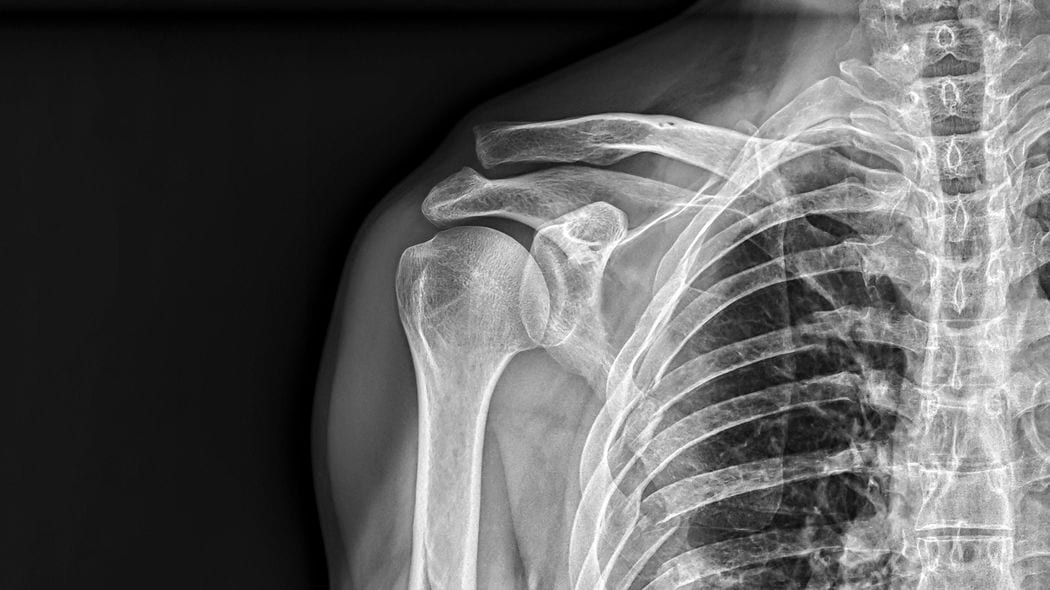

その時担当医が来て、レントゲン写真を見せながら説明を始めた。

「母の左側の肋骨は、12本のうち9本が折れており、3本にはひびが入っていて……こんなにボッキボキに骨折していても、コルセットを付けるぐらいしか処置の方法がありませんでした。また、医師は『お母さんは一人暮らしとのことですが、何もなければ2~3日で退院になる。退院後は実家で誰かが世話するのか、リハビリができる施設に身を寄せるのか、ソーシャルワーカーと相談してください』と言われました」